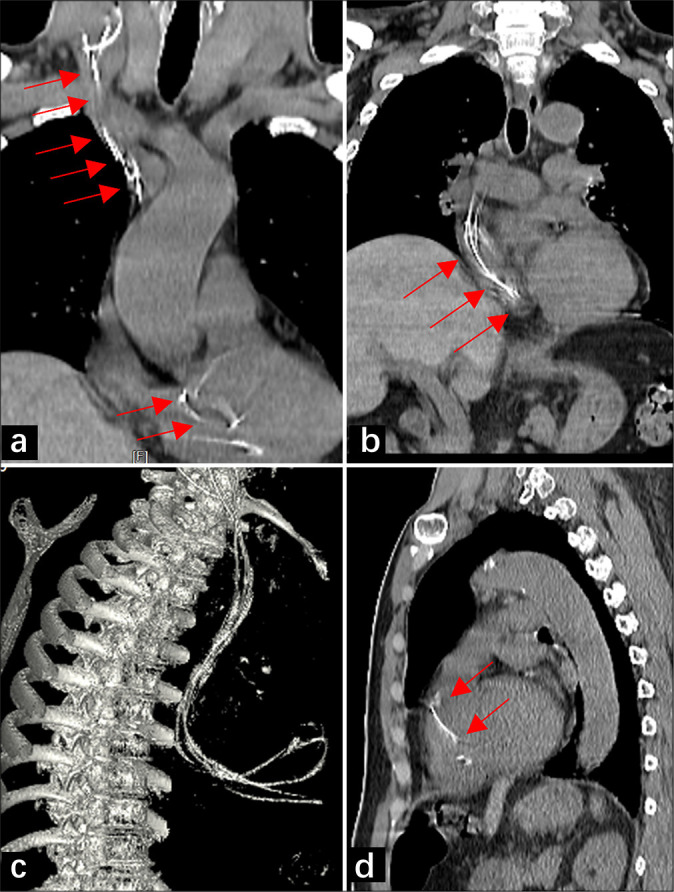

Ventriculoperitoneal (VP) shunts are commonly used to treat hydrocephalus by diverting cerebrospinal fluid from the ventricles to the peritoneal cavity. Migration of the VP shunt into the heart and pulmonary artery is a rare complication. Herein, we described a 67-year-old man with a VP shunt catheter that migrated through the venous system into the pulmonary circulation, highlighting early diagnosis with imaging and symptoms.

脑室-腹膜(VP)分流术通常用于脑积水的治疗,将脑脊液从脑室转移到腹膜腔。副静脉分流移入心脏和肺动脉是一种罕见的并发症。在此,我们描述了一位67岁的男性患者,他的VP分流导管通过静脉系统进入肺循环,强调了早期诊断的影像学和症状。